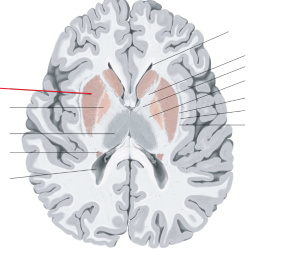

claustrum

nucleus caudatus

putamen

globus pallidus

capsula interna (corona radiata)

capsula externa

capsula extrema

hippocampus

amygdala